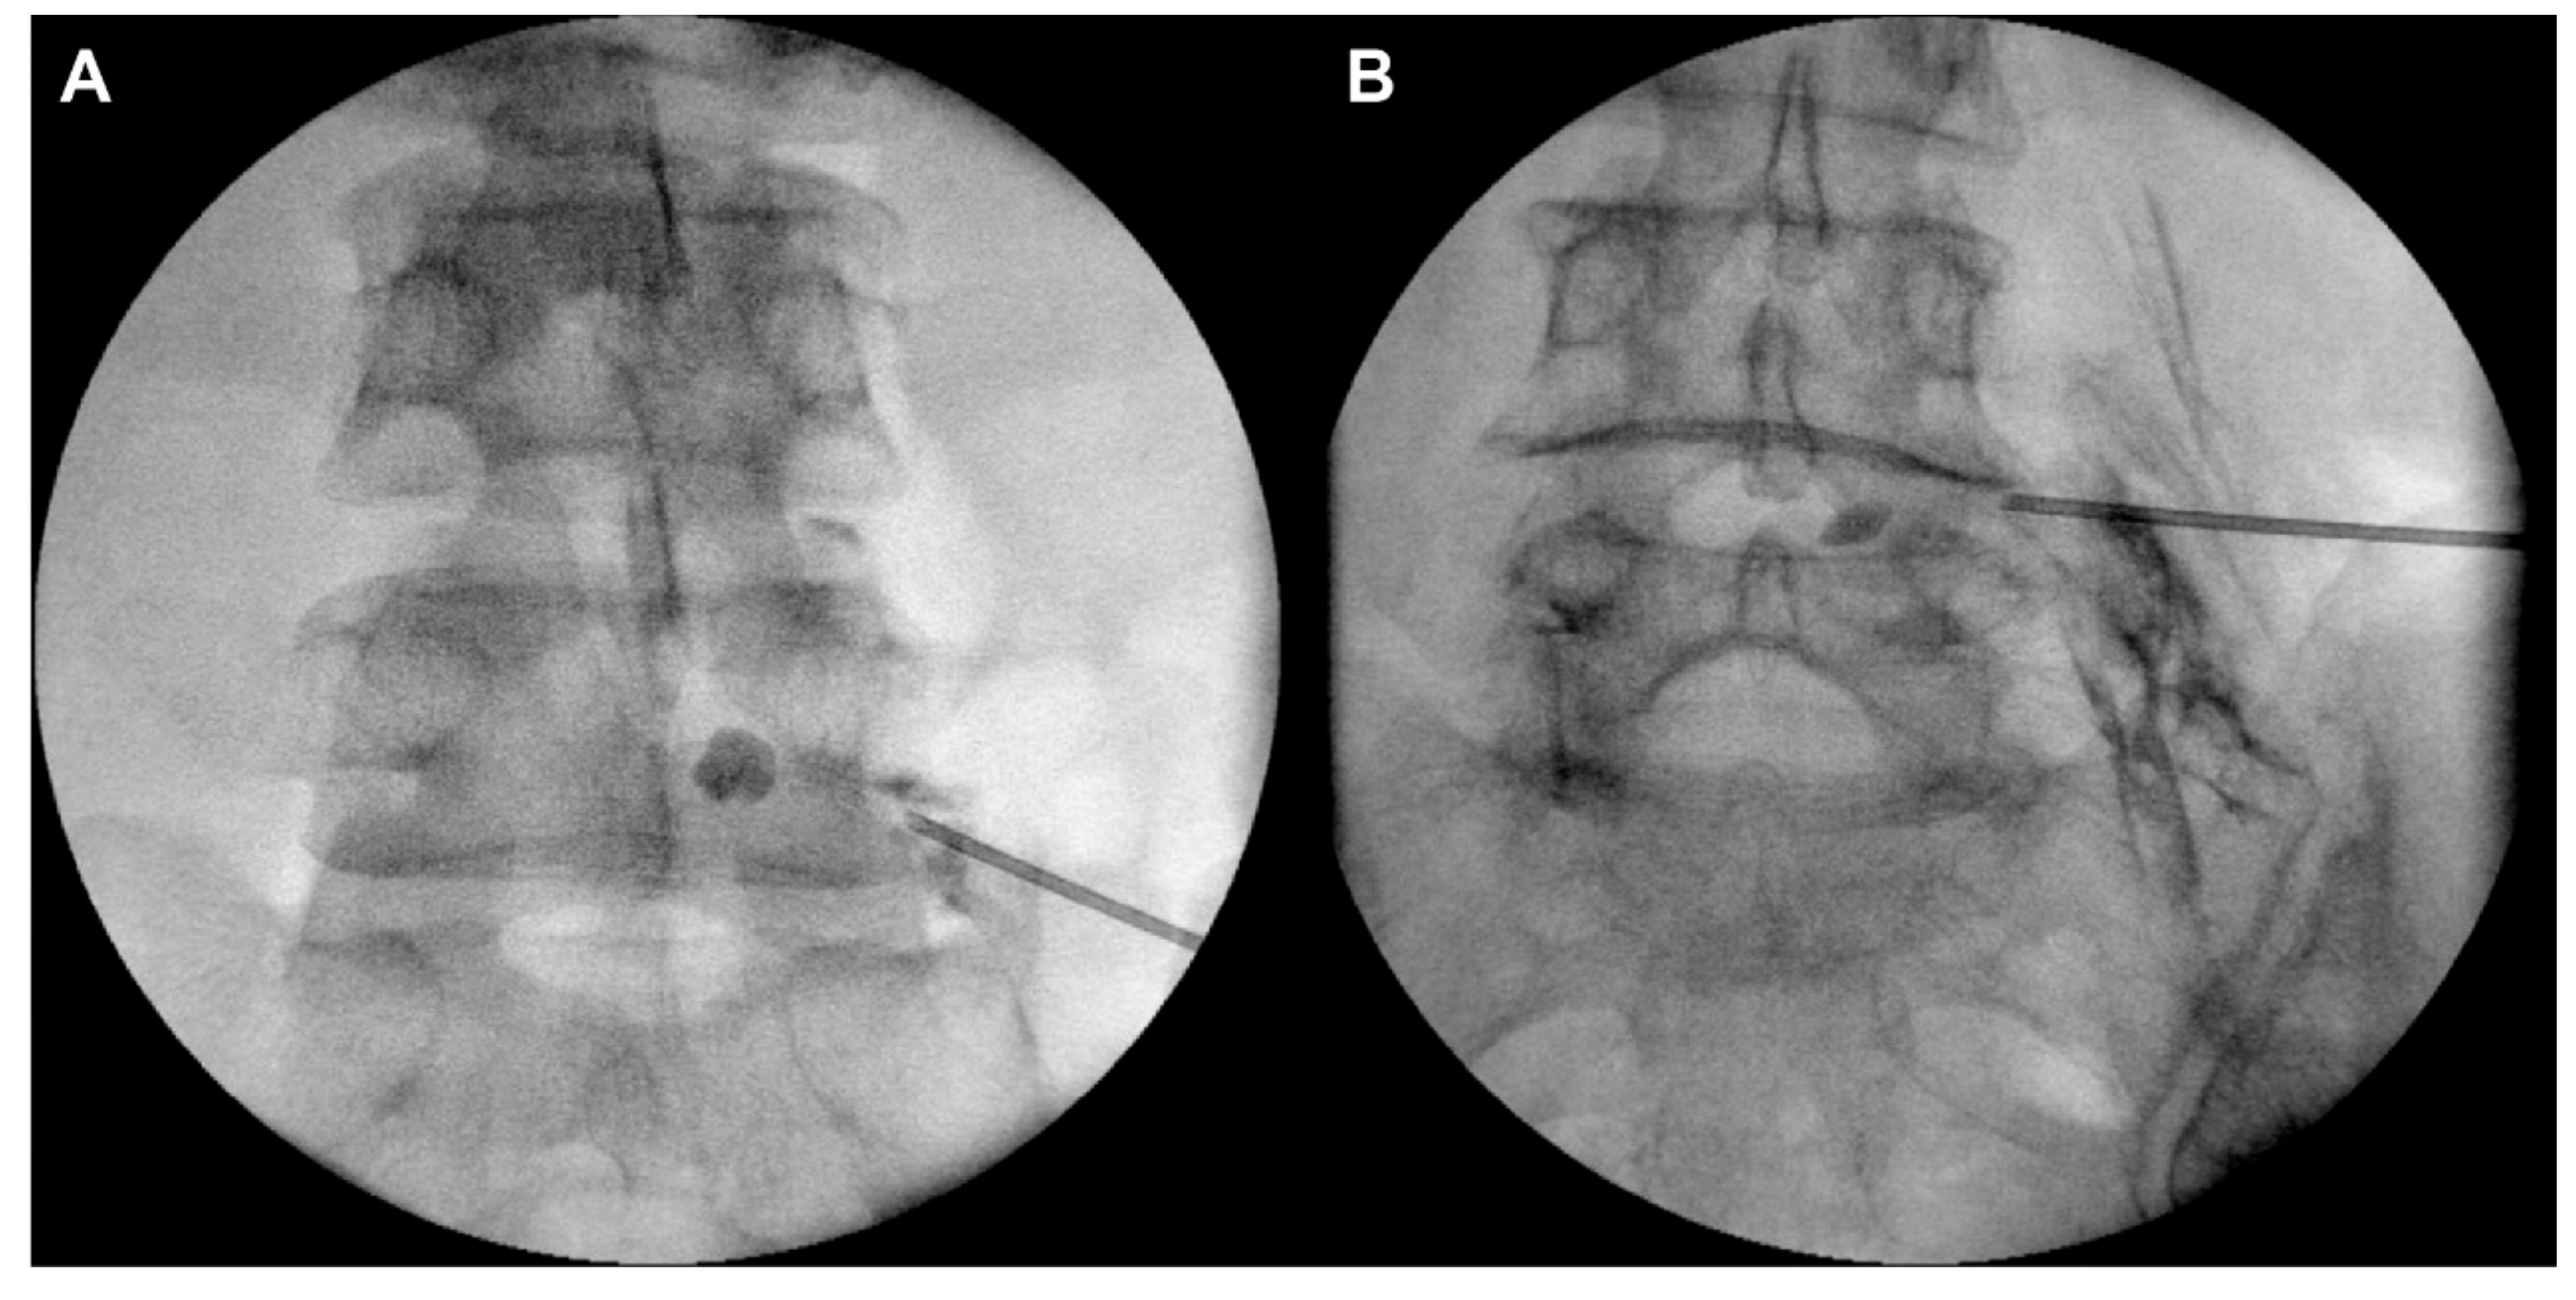

PTFA was performed using an inflatable balloon catheter with the safe-triangle approach or Kambin’s-triangle approach under fluoroscopy, by an experienced pain physician, who was blinded to the purpose and design of this study. In the traditional safe-triangle approach, a 16-gauge Tuohy needle (JUVENUI Co., Ltd., Seongnam, Republic of Korea) was inserted in the intervertebral foramen between L5 and S1 (just below the L5 pedicle). Fluoroscopy and contrast medium injection were used to check that the end of the needle had entered the anterior epidural space. In the Kambin’s-triangle approach, a 16-gauge Tuohy needle (JUVENUI Co., Ltd.) was inserted just above the superior articular process of L5 under oblique fluoroscopy (Figure 1 and Figure 2). In both cases, when the needle was positioned in the anterior epidural space, a 2-French inflatable balloon catheter (ZiNeu F: JVN_FC01, JUVENUI Co., Ltd., Seongnam, Republic of Korea) was inserted in the Tuohy needle. The correct positioning of the end of the balloon catheter in the narrowed epidural space around the L5 nerve root was verified. After the catheter had entered the target point, the tip of the Tuohy needle was retracted outside the intervertebral foramen to prevent loss and damage of the catheter and balloon. Inflation and deflation of the balloon from inside the lateral recess to outside the intervertebral foramen were repeated at a minimum of five consecutive points. Each balloon session lasted less than 5 s. The catheter was pre-filled with contrast media, and the maximal inflated balloon diameter was determined within 6 mm upon injecting 0.13 mL of contrast media. This inflation was repeated three times at each inflation point, considering the patient’s response. After the termination of inflation, the deflated balloon catheter was removed. Subsequently, the Tuohy needle was inserted in the anterior epidural space under fluoroscopy, and a 3-mL mixture of 0.18% ropivacaine, 1500 IU hyaluronidase, and 5 mg dexamethasone was injected.

Figure 1.

The safe-triangle approach (A) and the Kambin’s-triangle approach (B).

Figure 2.

Fluoroscopic anterior-posterior view of the safe-triangle approach (A) and the Kambin’s-triangle approach (B).